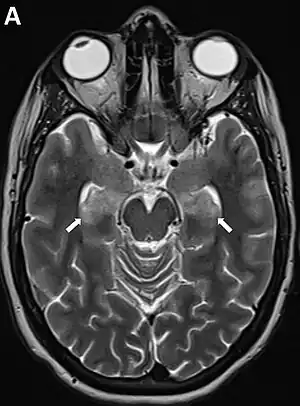

| MRI in FIRES showing changes in the mesiotemporal structures (arrow)[1] | |

The underlying cause is unclear.[2] Often there is an upper respiratory tract or gastroenteritis one day to two weeks before onset.[2] Diagnosis involves extensive testing to rule out other possible causes.[3][6] It may also be supported by MRI.[7] It is a type of new-onset refractory status epilepticus (NORSE).[6]